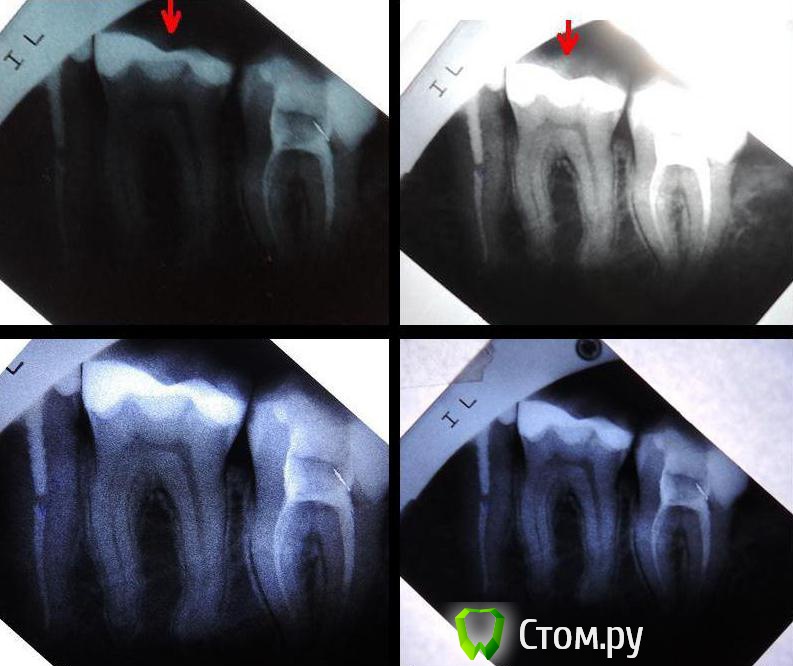

red_butler Опубликовано 8 апреля, 2014 Поделиться Опубликовано 8 апреля, 2014 С прилеганием не все гладко, требуется вкладка и коронкаhttp://i023.radikal.ru/1404/0d/2680f733b0e9.jpg Ссылка на комментарий

Wellen Опубликовано 8 апреля, 2014 Автор Поделиться Опубликовано 8 апреля, 2014 Спасибо за ответы!...Если Вы точно уверены, что болит 37 на сладкое, холодное и или горячее. То нужно проверить качество прилегания пломбы (по снимку нареканий нет) и провести холодовую пробу хладагентомБолит 36-ой (на снимке он посередине), 37 тоже болел после лечения, но его уже депульпировали. Про пробу - понятно. С прилеганием не все гладко, требуется вкладка и коронкаОго, действительно... Не обратила внимания на это место. Оно находится под десной, у самой кости. Обязательно переделывать на вкладку+коронку? И насколько это срочно? Этот зуб не беспокоит, после лечения каналов.А про соседний зуб что скажете? Болит сейчас именно он Ссылка на комментарий

red_butler Опубликовано 8 апреля, 2014 Поделиться Опубликовано 8 апреля, 2014 Что бы решить вопрос с 3.6 зубом нужен очный осмотр, проведение холодовой пробы хладагентом (эндофрост), возможно потребуется просто замена пломбы. Хорошо бы сделать цифровой снимок 3.7, что бы оценить качество пломбирования корневых каналов, ваш снимок не информативен. Протезирование 3.7 единственный способ сохранить зуб на долгие долгие годы. Ссылка на комментарий